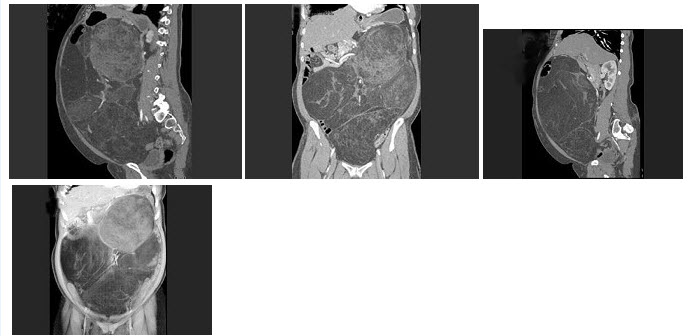

11、单项选择题

男,46岁,无痛性腹部肿块10月余,进行性增大伴消瘦2个月,结合图像,最可能的诊断是()